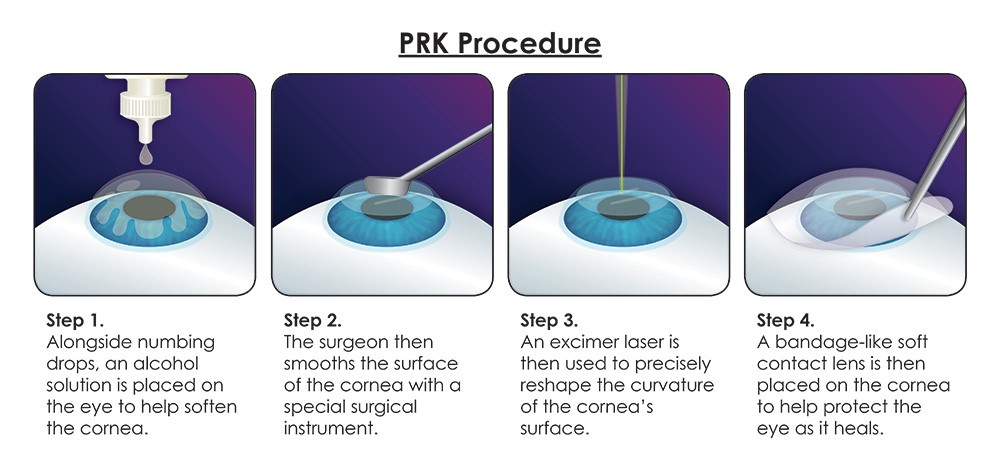

As técnicas básicas de aplicação do lase são o PRK e o LASIK.

PRK – abreviação do inglês “photorefractive keratectomy, o laser é aplicado após a remoção de uma fina camada superficial de córnea, o epitélio.

Após o laser, é colocada uma lente de contato gelatinosa terapêutica, que atuará como um curativo. Alguns pacientes poderão apresentar, no pós-operatório, embaçamento da visão por um período que varia de 1 a 15 dias e certo desconforto, até que o epitélio cicatrize e cubra a área tratada.